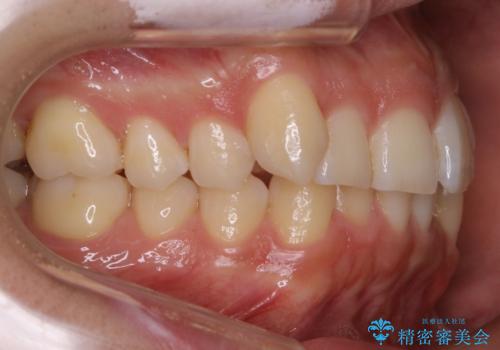

インビザラインで八重歯の治療

八重歯と噛み合わせえお治す必要がありましたが、抜歯を必要とするほどの状態ではなかったため非抜歯プランで治療を開始しました。

マウスピースとマイクロインプラントを組み合わせることで、抜歯をしなくても歯並びを治すためのスペースを作ることができます。奥歯から順に移動させていくので前歯に変化が出るまでには時間がかかりますが、その分健康な歯を抜歯することなく理想的な歯並びを手に入れることができます。